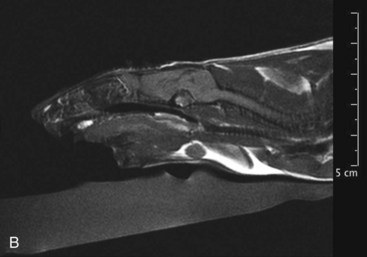

Mammary and Pituitary Tumors A, A pituitary tumor of a rat imaged with an MRI scan. B, The same tumor as in the previous image a few weeks after treatment with cabergoline. Note the significant shrinking of the tumor. (Photo courtesy Jörg Mayer, The University of Georgia, Athens.)